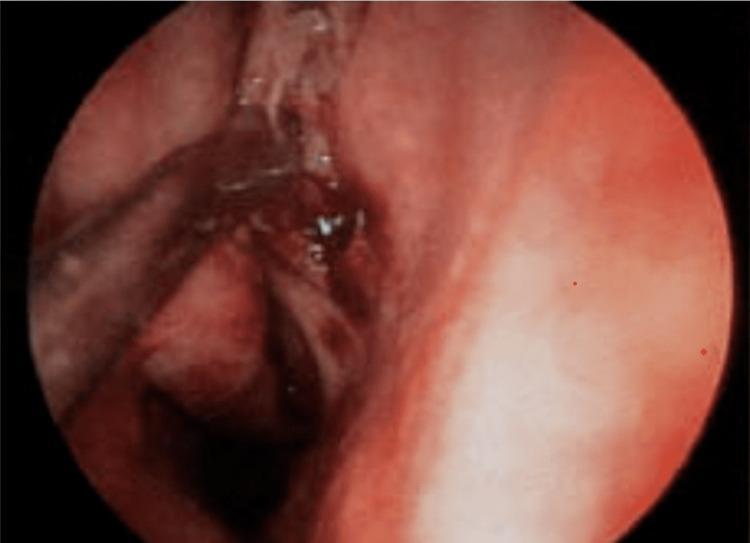

Introduction For endoscopic sinus surgery for rhinosinusitis, pre-emptive Alpha 2 agonist clonidine has been used to reduce sympathetic output, which lowers blood pressure and consequently surgical bleeding. The aim of this study was to analyze the effects of oral clonidine premedication in patients undergoing functional endoscopic sinus surgery. Methods This study was performed between December 2020 to November 2022 among two groups of 30 patients each: clonidine (200 μgm oral) and placebo. Parameters were recorded at baseline, 60 mins after administering the drugs, at induction, and at minutes five, 10, 20, 30, 45, 60, 75, 105, and 120. Six-point average category scale for bleeding was studied. IBM SPSS Statistics for Windows, Version 20.0 (Released 2011; IBM Corp., Armonk, New York, United States) was used for statistical analysis, and p < 0.05 was considered significant.  Results Demographic criteria were statistically non-significant. Heart rate (HR) and mean arterial pressure (MAP) were statistically non-significant at baseline and the 120th min mark, and were significant at other time intervals. The blood loss grading was less in the clonidine group, and the difference was found to be statistically significant (P < 0.001). Conclusion Pre-emptive oral clonidine 200 mcg 60 min prior to induction was found to reduce surgical bleeding by controlling haemodynamics.

https://cdn.ncbi.nlm.nih.gov/pmc/blobs/6e85/10202669/153bc4807841/cureus-0015-00000037918-i01.jpg